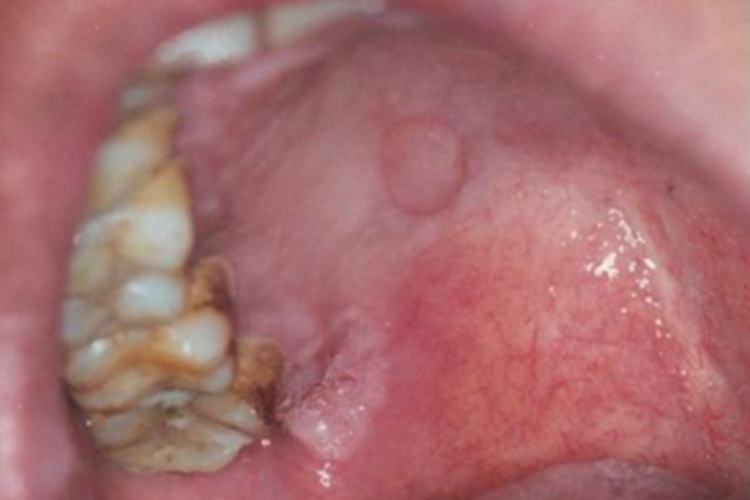

一期口腔梅毒口腔有个黄豆大小的类圆形溃疡,颜色以淡粉色为主,溃疡的边界明显并呈红色,而且溃疡面与周围黏膜平齐,患者无疼痛等不适症状。